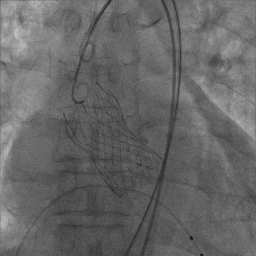

S3定位及植入

最终造影

(3)球扩瓣不同植入深度,将影响第一个瓣膜封堵区域(图8),本例患者在不影响二尖瓣前叶情况下,采用较深的植入深度:node 3-4之间(图9),最大限度规避冠脉堵塞风险,术后结果满意。